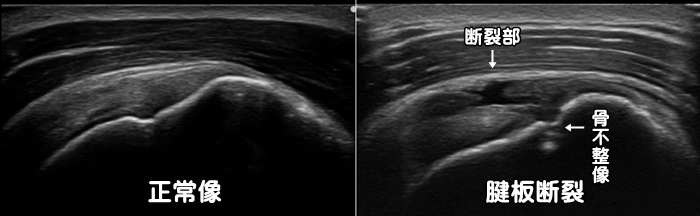

腱板断裂・滑液包炎・インピンジメント症候群

40代・50代での肩の痛みは四十肩・五十肩を疑います。しかし60歳以上で肩の痛みがある場合には肩の筋肉である腱板(棘上筋・棘下筋・小円筋・肩甲下筋)の断裂を疑います。四十肩・五十肩では腕を上げきった最後に痛みがありますが、腱板断裂では腕を上げる途中で痛みがあり、上げきると痛みが和らぎます。60歳以上の腱板断裂の原因の4割は外傷によるものですが、残り6割は日常生活で自然と断裂します。